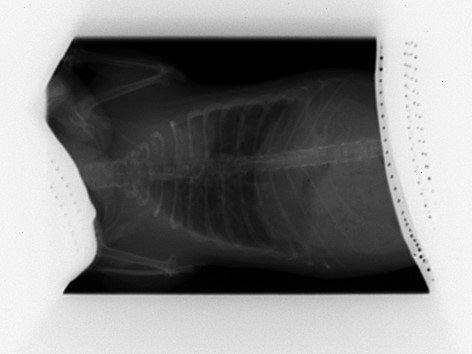

Découverte de multiples foyers infectieux dans les poumons :

Par radio, en janvier 2022.

A ce stade le véto n'est pas inquiet, car bien que multiples les tâches sont très infimes et les poumons restent intègres ; il me recommande de la surveiller de très près et me prévient que si une décompensation doit se faire se sera surement silencieusement (donc surveillance du poids et du mouvement respiratoire).

Le 25 mai je fais faire les radios de contrôle car je la trouve un chouya plus fine des flancs et on observe que l'aspect des foyers infectieux est plus "moucheté" ; c'est pas la cata encore (poumons toujours intègres) mais comme y'a tout de même évolution on commence le traitement : Doxy pour au moins deux semaines.

Voilà les radios ; pour chaque ligne :

• à gauche = janvier

• à droite = mai

KISS 2022 01 03 (1).jpgKISS 2022 05 25 (2).jpg

KISS 2022 01 03 (2).jpgKISS 2022 05 25 (1).jpg

• La radio montre que son cœur est légèrement décollé de l'endroit où il devrait être, mais sans que ça soit un soucis.